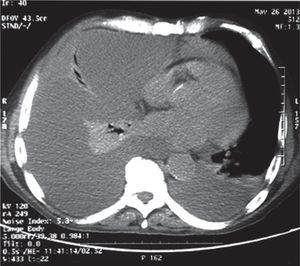

Presentación de casoPaciente masculino en la octava década de la vida, 72 años, de ocupación agricultor, quien ingresa al servicio de urgencias por presentar cuadro clínico de un mes de evolución, consistente en dolor de aparición progresiva en hemitórax derecho que se exacerba durante la inspiración y se irradia a horquilla esternal, asociado a disnea progresiva de pequeños a medianos esfuerzos, odinofagia. Cuatro días previos al ingreso presenta exacerbación de los síntomas, asociado a lesión eritematosa y descamativa en la cara (fig. 1A) y en la zona de exposición solar en tórax (fig. 1B) además de edema periorbitario en manos y miembros inferiores. Como antecedentes de importancia refiere exposición prolongada al humo de leña. Como hallazgos positivos al examen físico presentaba inyección conjuntival, edema periorbitario, mucosa oral seca con úlceras de fondo limpio, expansibilidad del tórax asimétrico, con movimientos respiratorios disminuidos en hemitórax derecho, así como ruidos respiratorios velados de forma ipsilateral, ruidos cardiacos taquicárdicos de intensidad disminuida y edema grado II con fóvea en miembros inferiores. En la química sanguínea se evidenció leucopenia y proteína C reactiva (PCR) elevada. Posteriormente, se realizó ecocardiograma transtorácico que reportó fracción de eyección del ventrículo izquierdo conservada y radiografía de tórax (figs. 2A y 2B) que documentó derrame pleural masivo en hemitórax derecho con desviación de la tráquea ipsilateral. Se realizó toracentesis diagnóstica y evacuatoria que demostró exudado linfocítico; los estudios para mycobacterias (reacción en cadena de polimerasa y cultivo) fueron negativos; así mismo se realizó estudio imaginológico con escanografía de tórax con el fin de descartar etiología neoplásica (fig. 3), además de bloque celular y estudio citológico los cuales fueron negativos para neoplasia, en el TAC de tórax se confirmó la presencia de derrame pleural derecho y derrame pericárdico sin evidencia de lesiones de características tumorales. Dada la presencia de derrame pleural y hallazgos en piel, se consideró relevante descartar compromiso autoinmune tipo lupus eritematoso sistémico con actividad, por lo que se solicitaron estudios adicionales que reportaron ANAS y anti DNA positivos con complemento consumido (tabla 1). Debido a los hallazgos inmunológicos y cuadro clínico de poliserositis asociado a compromiso cutáneo, hematológico por leucopenia con linfopenia y eritema malar, ulceras orales, se consideró cuadro compatible con lupus eritematoso sistémico del anciano, por lo que se ampliaron estudios con base en detección de compromiso renal, el cual fue negativo. Se inició manejo inmunomodulador con esteroides con el cual el paciente presentó mejoría clínica y fue dado de alta.